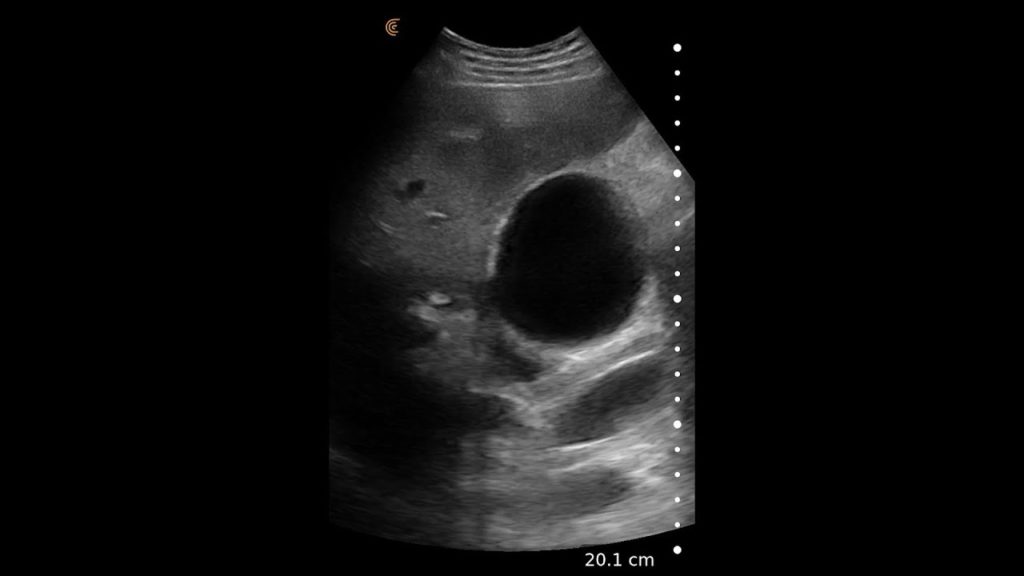

Using the jejunum as an important landmark, the hypoechoic jejunal lymph nodes can be identified. In this video Dr. Edwards explains the ultrasound appearance of normal jejunal nodes.